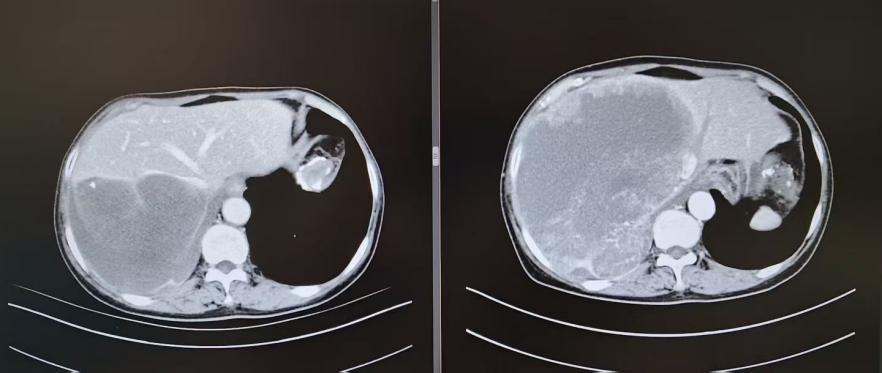

治疗后:胸部+腹部增强ct

数月的规范治疗后,转机悄然出现:李霞的剧烈疼痛显著缓解,复查显示肿瘤由“热”变“冷”,活性减低,体积缩小至19×16×13cm。更重要的是,原本与心脏、大血管紧密粘连的肿瘤,形成了数毫米的“安全间隙”,剩余肝脏体积得以增生——这道微弱却珍贵的间隙,也成为手术切除的唯一突破口。在多学科团队再次会诊后一致判定:已具备手术切除条件,必须抓住这一难得的“窗口期”。